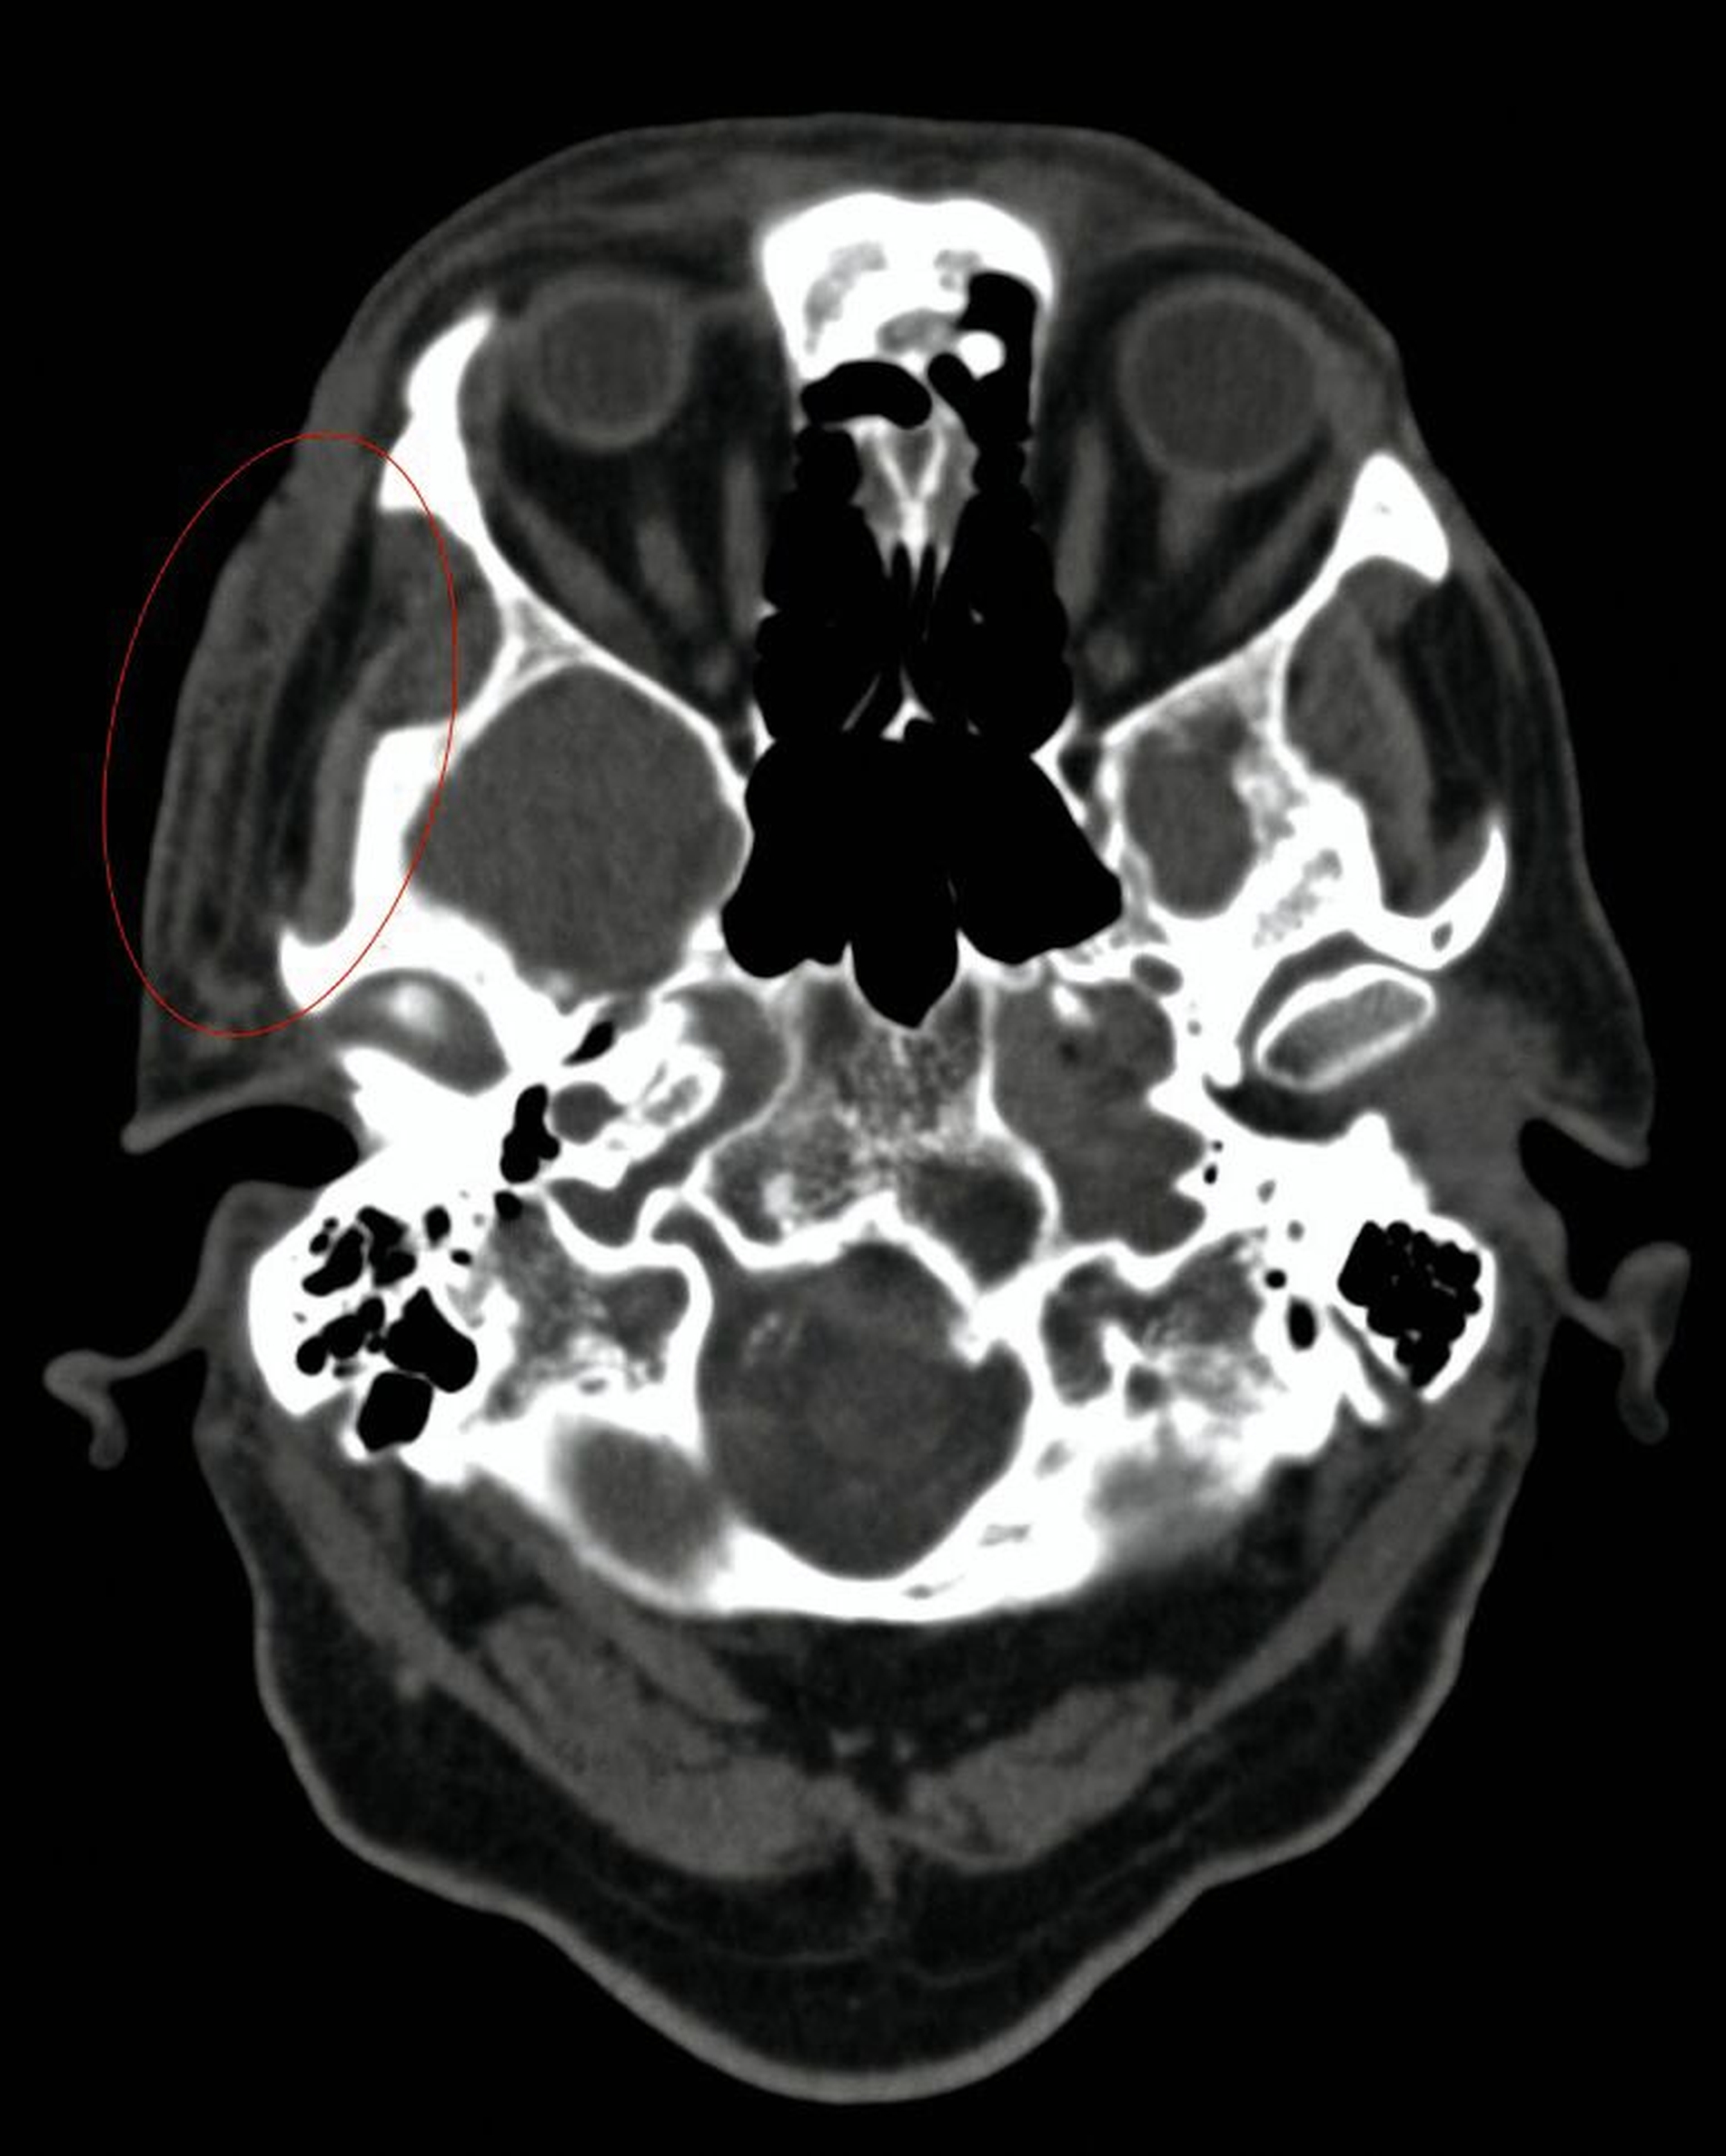

Aufgrund des klinisch-makroskopischen Bildes mit progressiver Gewebenekrose, fehlender segmentaler wasserklarer Bläschen wurde der Zoster durch PCR ausgeschlossen und die antivirale Therapie beendet. Ein maligner Tumor fand sich in der Probeexzision vom Aufnahmetag nicht. Ebenso wurde per Computertomografie (CT) und Magnetresonanztomografie (MRT) eine intrazerebrale und intraorbitale Beteiligung ausgeschlossen. Allerdings zeigten sich rechts temporoparietal eine zunehmende Dichteanhebung, paraseptale Lufteinschlüsse und eine Schwellung des Weichgewebes mit progredienter Ausweitung im Vergleich zu den Aufnahmen einen Monat zuvor (Abbildungen 2 und 3). In der Zusammenschau von Klinik, Bildgebung und dem positiven Befund eines Staphylococcus aureus in der zwischenzeitlich erfolgten mikrobiologischen Analyse wurde die Diagnose einer akut nekrotisierenden Fasziitis gestellt.

Im fortgeschrittenen Stadium lässt sich eine Krepitation der Weichteile vernehmen, die radiologisch als eingeschlossene Luftblasen verifizierbar ist. CT und MRT sind somit wichtige Hilfsmittel, um Differenzialdiagnosen auszuschließen und die Ausbreitung in den Weichteilen und auf Faszienebene abzuschätzen, lange bevor kutane Nekrosen sichtbar sind [Wysoki et al., 1997].

Die Maden-Therapie stellt in unseren Augen jedoch einen besonderen Therapieansatz und nicht das Regelvorgehen dar. Sie sollte in unseren Augen bei der nekrotisierenden Fasziitis immer nur dann zur Anwendung kommen, wenn es die Ausdehnung des Befunds noch zulässt. In unserem Fall lag zwar ein ausgedehntes und mit kritischen anatomischen Strukturen beteiligtes Wundareal vor, die Infektion lag jedoch lediglich im Bereich der superfizialen, gut durchbluteten Gesichtsweichteile und war daher der Maden-Therapie zugänglich. Eine Beteiligung tieferer Strukturen (Orbita, Muskelnekrosen) war CT-morphologisch vorab ausgeschlossen worden.